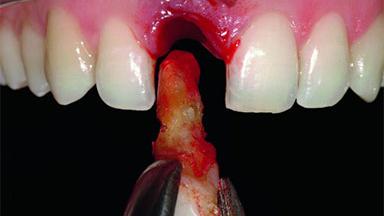

A 32-year-old female Caucasian patient with a compromised maxillary right central incisor was referred to us by a general dentist. Her chief complaints were discomfort and mobility of tooth 11 with unsatisfactory esthetics due to discoloration. The patient reported a previous trauma, some years earlier, as the origin of pathology on the afflicted tooth. Anamnesis was negative for any other dental or periodontal pathology in the remaining dentition. The patient did not take any medication and reported to be a light smoker (5–10 cigs/day). She had high esthetic expectations of her treatment. The extraoral examination revealed a high smile line with full exposure of her maxillary teeth and surrounding soft tissue in the area between the second premolars.